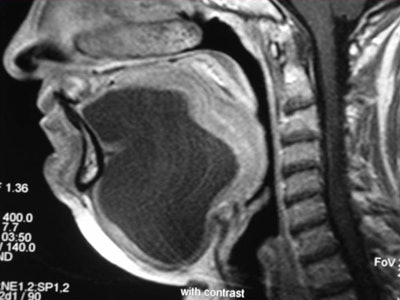

CT and MR are currently the primary imaging modalities to assess the oral cavity. CT is preferred in patients presenting with infectious/inflammatory syndrome. According to Borges, in patients presenting with oral cavity cancer, the use of dental CT software with the acquisition of para-axial and parasagittal high-resolution images in bone algorithm is most valuable in depicting early cortical bone erosion. MRI provides better soft-tissue resolution, and is the first choice in evaluating the deep extent of tumors and for the management of patients presenting with submucosal lesions.

Referring to the choice of imaging technique, she highlights the importance of considering different patients' specificities. Heavy smokers and drinkers prone to salivary stasis, difficulty in swallowing, and dyspnea are not good candidates for MRI, as this technique is very prone to motion artifacts, and patients with many dental fillings and/or dental implants may do better with MRI than with CT, she explained.

In terms of technical issues to note when imaging the oral cavity, Borges has plenty of good advice. She points out that dental-related artifacts can be avoided by angling the axial sections parallel to the dental fillings on CT or opting for MRI. When lesions are located in the gingival sulcus, jugal or palatal mucosa, or the tongue, cheek puffing is very helpful to clearly depict the full extent of the lesion and separate the lesion from the adjacent mucosal surfaces, she noted.

Whenever imaging a malignancy, the full extent of the neck should be imaged for nodal staging. Bone windows are required for all cases of cancer staging and whenever dentomaxillary pathology is suspected.

Finally, she emphasized that when using MRI, it is crucial to instruct a patient not to swallow and to breathe quietly during the entire examination. The use of surface coils can be very helpful for the imaging of superficially located lesions such as the parotid and submandibular glands and the floor of the mouth.